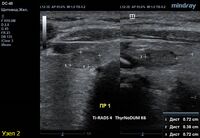

2) Узел у перешейка, не прорастает капсулу щитовидной железы (0 баллов), больше широкий чем высокий (0 баллов), не имеет кальцинатов (0 баллов), с ровным четким контуром (0 баллов), гипоэхогенный (2 балла), тканевой структуры (2 балла). Количество баллов 4, ACRTi-RADS4, ThyrNoDUMК6. Пункция не показана в связи с малым диаметром узла (более 1,5 см для Ti-RADS4), рекомендовано наблюдение.